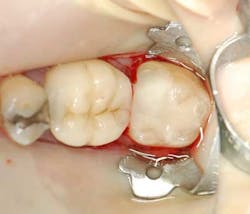

A 55-year-old male patient presented with a chief complaint of occasional hot and cold sensitivity involving his lower molar. Upon clinical examination, it was determined he had a failing amalgam and undermined mesial buccal cusp involving his second molar (Fig. 1). As per the Morgan and Presley’s prewedge protocol, a medium wedge was placed between the molars to initiate separation and protect the papilla. Upon removal of the old restoration and decay, it was decided to restore this tooth with a posterior composite material using the ABC Wedge. With a little imagination, this wedge looks like an elephant’s head and its parts will be described as such. The ears were designed to support the sectional band in three dimensions (3-D) and prevent the sectional rings from crushing in the matrix band (Fig. 2). The elephant’s trunk is analogous to the anatomic wedge. Two wedges were used from the buccal and lingual surfaces, and the curved trunks slide past each other to seal off the gingival floor (Fig. 3). A central groove is located on the back between the ears to line up the sectional separating ring and directs the pressure interproximally for maximum separation. The tooth was then easily restored in incremental layers, trimmed back, and the bite was adjusted (Fig. 4).

Fig. 1 — Failing amalgam and undermined cusp.